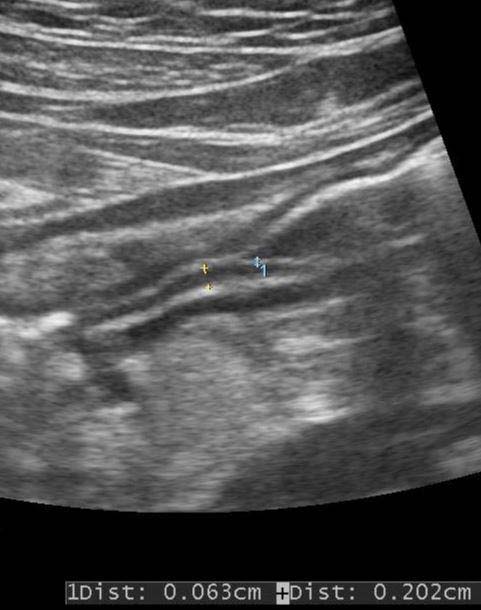

Sonographic evaluation of the stomach was performed by an experienced Sonologist using a convex (3-5 MHz) probe, followed by a linear transducer (7-12 MHz) after obtaining Oral Informed Consent. (Figures 1, 2)

Whole Stomach wall thickness and thickness of individual layers (S1-S5), was measured in the crosssection, in the longitudinal section at the level of superior mesenteric Artery.

The thickness of gastric layers on ultrasound are labeled as (Figures 3,4) S1-Mucosa. S2-Muscularis mucosa S3-Submucosa S4-Muscularis propria S5-Serosa & Whole wall thickness in the gastric antrum.

The thickness of individual layers-Layer 1, Layer 2, Layer 3, Layer 4, Layer 5, total The thickness of Gastric wall (including layers 1 to 5), were obtained in 20 Controls (normal ) and 20 patients of gastritis. The ratio of Layer 2 to the full the thickness of the gastric wall was obtained in Controls and Patients of Gastritis. In Control group (Figures 3, 4)

? The thickness of Layer 5 was 1 mm ? The Combined thickness of Layer 1 and 2 was 1.9 to 2.1 mm. ? Total thickness of the Gastric wall (Layer 1-5) was 6.9 mm to 7.4 mm. ? Ratio of the thickness of Layer 2 to total wall thickness was 0.12 to 0.15 In Acute Mild Gastritis group-(Figures 5, 6)

Endoscopy) The thickness of Layer 1 was less than 1 mm

? The thickness of layer 2 was 2 to 3 mm ? The thickness of layer 3 was 2 mm to 2.3 mm ? The thickness of layer 4 was 2 mm

? The thickness of layer 5 was 1 mm ? The combined thickness of layer 1 and 2 was 3-4 mm. ? Total thickness of the Gastric wall (layer 1-5) was 8 mm to 9.2 mm. ? Ratio of the thickness of Layer 2 to the total gastric wall thickness was 0.25 to 0.33 Thus, in Patients of Mild Gastritis, there was thickening of layer 2.

Thickening of Layers 1 and 2 and total gastric wall thickness was statistically significant. Ratio of the thickness of Layer 2 to a total Gastric wall thickness was statistically significant.

A penetrating Ulcer may extend up to Serosa, in cases of impending perforations. Hence all five layers are involved. 3 Gastritis can be acute and chronic. Acute gastritis can be mild and severe. In mild Acute Gastritis, the surface epithelium is intact. The mucosa is hyperaemic, oedematous, congested and red. Histologically, there are intraepithelial and intraluminal neutrophils. In severe acute gastritis, there are mucosal erosions with resultant loss of surface epithelium, hemorrhages seen as punctate dark spots with inflammatory and fibrino us purulent exudates. Acute erosive hemorrhagic gastritis is characterized by concurrent erosion and hemorrhages with extensive mucosal damage and is commonly seen in alcoholic and NSAID users. 4,5 Acute gastritis is caused by H. Pylori, other infectious causes (like bacteria, viruses, fungi and parasites), and non-infective gastritis. Chronic gastritis can be Type A (AutoImmune-Body-fundic predominant), Type B (H. Pylori related-Antral predominant), Type AB (Environmental-Antral-body predominant), Chemical (Reflux-Antral-body predominant) and uncommon forms of gastritis. [6][7][8] In Patients of Mild Acute Gastritis, there is a thickening of layer 2 and total gastric wall thickness, on ultrasound. The ratio of the thickness of Layer 2 to total Gastric wall thickness is significant. 9 Our observations indicate that transabdominal Ultrasound with Convex Probe, followed by Linear Probe, can predict diagnosis of Mild Gastritis and can reduce the number of Endoscopic Evaluations and further Ulcer formations. It can predict associated mucosal erosions if Layer 1 thickness is less than 1 mm with associated thickening of layer 2. In our case series, 5 cases of gastric erosions were detected on Ultrasound and were confirmed on gastroscopy.